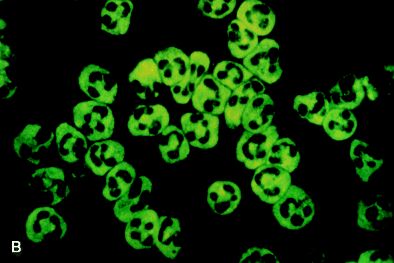

2. Anticuerpos

1. C-ANCA

1. Citoplasma

1. Antígeno

1. Proteinasa 3

2. P-ANCA

1. Perinuclear

1. Mieloperoxidasa

2. X-ANCA

1. Atípicos